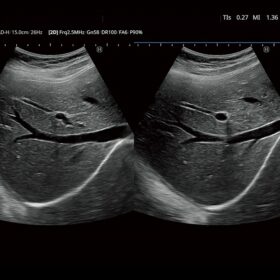

FUTUS features great imaging technologies to support a clear view and confident diagnoses.